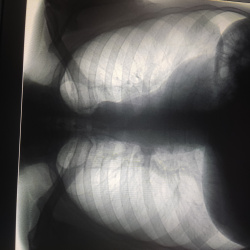

Добрый день. Подскажите пожалуйста в правом кардио-диафрагмальном углу что за тени? участки обызвествлений хрящевой части ребер ?